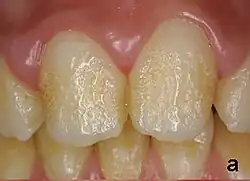

Pitting enamel hypoplasia

Enamel hypoplasia can take a variety of forms, but all types are associated with a reduction of enamel formation due to disruption in ameloblast production.[1] One of the most common types, pitting enamel hypoplasia (PEH), ranges from small circular pinpricks to larger irregular depressions.[2] Pits also vary in how they occur on a tooth surface, some forming rows and others more randomly scattered.[3] PEH can be associated with other types of hypoplasia, but it is often the only defect observed.[4] Causes of PEH can range from genetic conditions to environmental factors, and the frequency of occurrence varies substantially between populations and species, likely due to environmental, genetic and health differences. The most striking example of this is in Paranthropus robustus, with half of all primary molars, and a quarter of permanent molars, displaying PEH defects, thought to be caused by a specific genetic condition, amelogenesis imperfecta.[1]